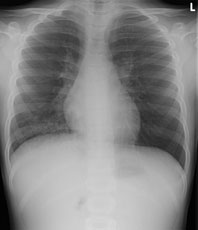

Zur Aufnahme kommt ein 8 jähriger Knabe mit hartnäckigem, vorwiegend trockenem Reizhusten seit 5 Tagen und subfebrilen Temperaturen bis mässigem Fieber.

Bei relativ blander Klinik wird ein Thoraxröntgen durchgeführt:

Thorax pa

Bild vergrössern